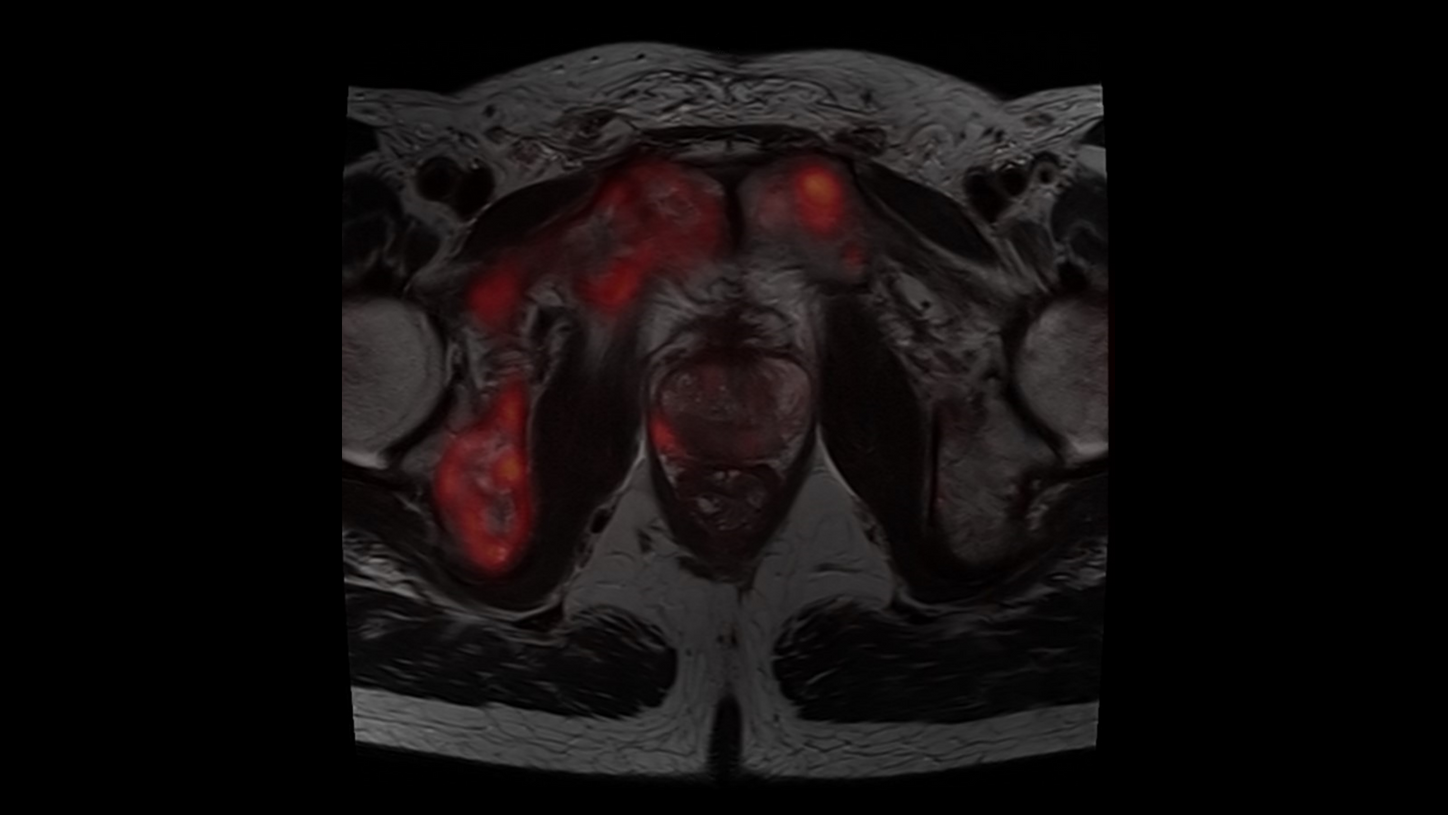

BIOGRAPH One excels in PET/MR precision to support confident diagnostic decisions. Featuring the Optiso UDR Pro detector with the largest 35 cm axial FOV2 and the best time resoulution2 in PET/MR, it enables comprehensive capture with excellent sensitivity and ultra-fast TOF3 in real time 鈥 delivering exceptionally clear, detailed images even in low-dose settings.

With Deep Resolve for accelerated acquisition and improved resolution in 2D and 3D applications4, BIOGRAPH One makes PET/MR exams faster than ever before. With an exceptional 3T magnet at its heart, BIOGRAPH One delivers unparalleled performance with outstanding homogeneity, a large 55 x 55 x 50 cm鲁 field of view and robust gradient power.